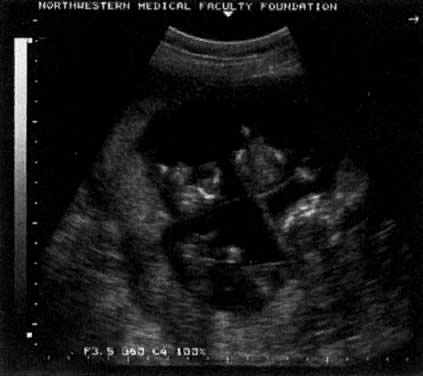

The determination of chorionicity of multiple gestations is of obvious interest to the obstetrician because of the greatly increased morbidity and mortality in monochorionic pregnancies and in particular monoamniotic-monochorionic twin pregnancies. In a well-illustrated study, Monteagudo and co-workers20 demonstrated the extreme reliability of first-trimester ultrasound in predicting chorionic and amniotic type (Fig. 10). Sepulveda and associates,21 in a series of 288 twins, correctly identified all 63 monochorionic twins at 10 to 14 weeks using the lambda sign, which is a triangular projection of placenta where dichorionic placentas meet (Fig. 11). Sepulveda and colleagues22 also described the ipsilon zone, where the chorionic membranes converge centrally, which is useful in identifying the chorionicity of most triplet pregnancies (Fig. 12).

Fig. 10. A monochorionic twin pregnancy. A separating membrane was noted on a later ultrasound.